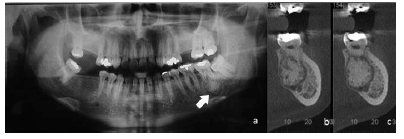

Homem de vinte e cinco anos de idade, melanoderma, compareceu a unidade odontológica para a remoção de terceiro molar superior. Por imagem radiográfica, constatou-se aumento de volume radiopaco fundido ao ápice do dente 37 circundado por um fino halo radiolúcido, conforme indicado pela seta na imagem radiográfica a. Foi solicitada a realização de tomografia, para confirmação das características previamente identificadas. As imagens da tomografia correspondem às indicadas pelas letras b e c.

Considerando-se o aspecto patognomônico da lesão, é correto afirmar que se trata de